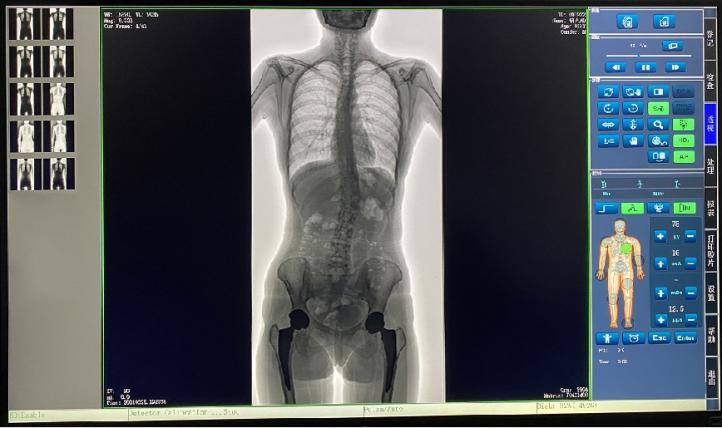

普愛醫(yī)療新推出一款動態(tài)平板DR-PLX8600,這款產(chǎn)品可攝影、可透視、可造影,臨床適用范圍廣泛,可滿足不同臨床拍攝需求。一體式的機架,擺位簡單快捷,不僅融合了市面上17英寸動態(tài)DR的所有功能,還有獨具特色的超大動態(tài)視野范圍,給臨床應用帶來醫(yī)療診斷價值,降低醫(yī)院設備投入成本,獲得更大收益。

1.專為大視野臨床應用打造的平板動態(tài)DR,圖像不拼接,有效簡化影像科室檢查流程,提高診斷精度,降低患者吸收的輻射劑量。

2.解決了拼接圖像存在密度不均勻,拼接處圖像配準和放大效應等問題,輻射劑量小。

7.自研軟件系統(tǒng),功能區(qū)劃分合理,操作便捷,圖像處理清晰。